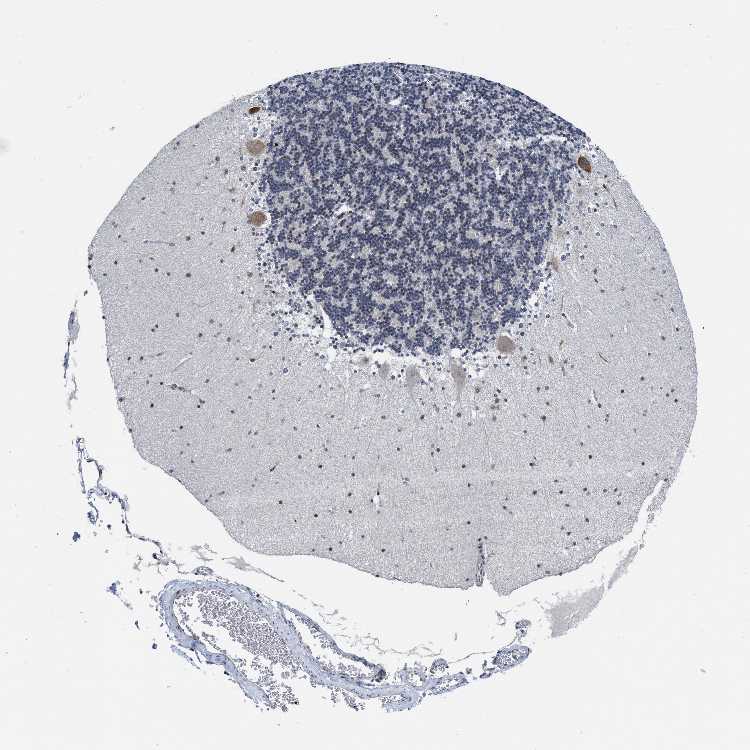

BRAIN CEREBELLUM Show tissue menu

CEREBELLUM - Expression summary

CEREBELLUM - Antibody stainingi

Antibody staining in the annotated cell types in the current human tissue is reported as not detected, low, medium, or high, based on conventional immunohistochemistry profiling in selected tissues. This score is based on the combination of the staining intensity and fraction of stained cells.

Each image is clickable and will lead to virtual microscopy that enables deeper exploration of all samples and also displays staining intensity scores, fraction scores and subcellular localization as well as patient and tissue information for each sample.

Antibody HPA001275Antibody CAB017442

Purkinje cells Not detectedMedium

Cells in granular layer LowLow

Cells in molecular layer Not detectedMedium